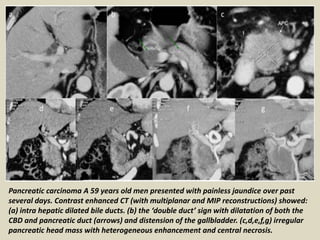

Pancreatic carcinoma A 59 years old men presented with painless jaundice over past

several days. Contrast enhanced CT (with multiplanar and MIP reconstructions) showed:

(a) intra hepatic dilated bile ducts. (b) the ‘double duct’ sign with dilatation of both the

CBD and pancreatic duct (arrows) and distension of the gallbladder. (c,d,e,f,g) irregular

pancreatic head mass with heterogeneous enhancement and central necrosis.